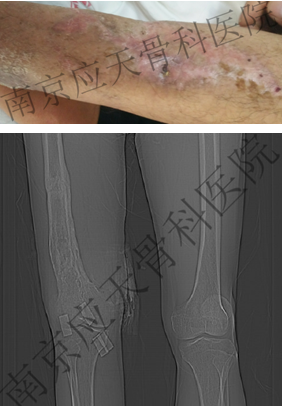

术前:

术后: